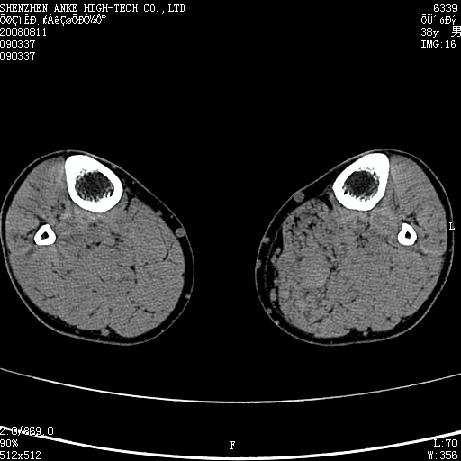

患者,男,38岁,右小腿疼痛性包块1月,查体:右小腿可扪及约5x4cm大小包块,压痛.

左小腿内侧软组织病变,性质待定(血管瘤?);建议行mri检查。